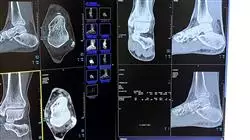

Una delle patologie più frequenti negli ambulatori di ortopedia e traumatologia è l'alluce valgo. Le calzature inadatte, sempre più utilizzate nel mondo occidentale, hanno aumentato il numero di pazienti affetti da questi problemi. Tuttavia, i progressi tecnici hanno permesso la correzione chirurgica attraverso diverse tecniche utilizzate a seconda della gravità del caso.

A tal fine, questa istituzione accademica si avvale di un personale docente composto da specialisti in Traumatologia e Ortopedia, che forniscono le informazioni più avanzate e complete attraverso un programma teorico e pratico. Lo specialista potrà, in questo modo, approfondire la deformità dell'alluce valgo o bunion, il problema dell'alluce rigido o artropatia della prima articolazione metatarso-falangea, la deformità dell'alluce varo e i problemi del sistema o complesso sesamoideo.

Noi della TECH Università Tecnologica sappiamo che il tuo tempo è prezioso e che hai bisogno di un'opzione flessibile per continuare il tuo sviluppo professionale. Per questo motivo il nostro corso si svolge online, permettendoti di accedere ai contenuti da qualsiasi luogo e nel momento più adatto alle tue esigenze. La formazione online ti dà la libertà di apprendere secondo i tuoi ritmi, senza rinunciare alla qualità educativa. Iscrivendoti al nostro Corso Universitario in Chirurgia dell'avampiede: Patologie del Primo Raggio, beneficerai dell'esperienza dei nostri rinomati professionisti nel campo della podologia e della chirurgia podologica. Durante il programma acquisirai conoscenze aggiornate sulle tecniche chirurgiche più avanzate per trattare patologie come l'alluce valgo, il dito a martello e altre patologie che colpiscono il primo raggio del piede. Inoltre, imparerai a eseguire valutazioni cliniche precise, interpretare studi radiologici e pianificare in modo personalizzato il trattamento chirurgico più appropriato per ciascun paziente. Il nostro approccio pratico ti consentirà di applicare le conoscenze acquisite attraverso casi clinici e simulazioni virtuali, dandoti la sicurezza necessaria per realizzare interventi di successo nella tua pratica professionale. Distinguiti nel tuo campo ed espandi le tue competenze nella chirurgia dell'avampiede con il supporto accademico della TECH Università Tecnologica . Iscriviti al nostro Corso Universitario in Chirurgia dell'Avampiede: Patologie del Primo Raggio e diventa un professionista altamente qualificato nel trattamento chirurgico delle patologie del primo raggio del piede. La tua crescita professionale inizia da qui!